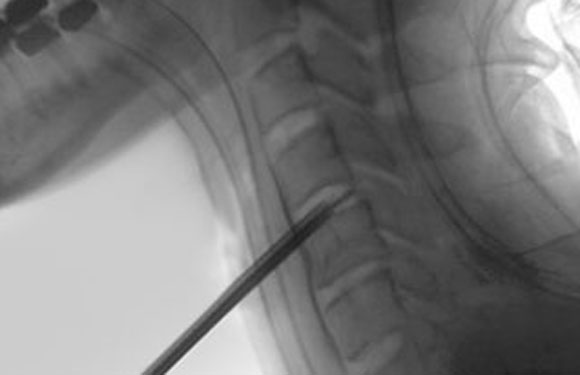

Click to watch a video that shows the back of a cervical disc space with a fragment of herniated disc being removed and the back of a decompressed disc space with the dura pulsating over the spinal cord.